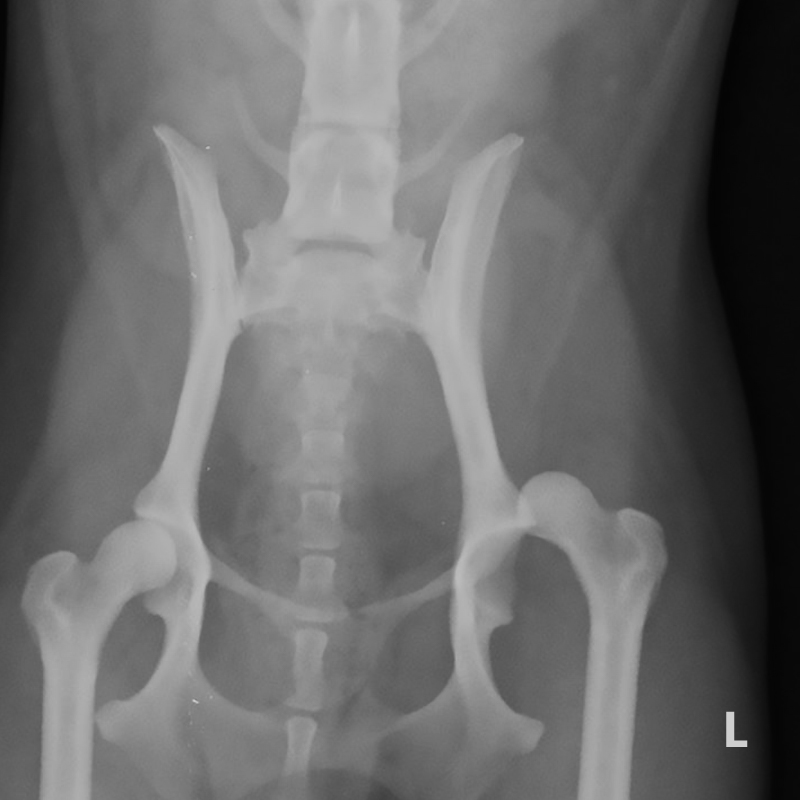

Radiography showing bilateral coxofemoral luxation (arrows) in a dog Hip Joint Luxation Dog dogs who are free fed are more likely to become overweight and develop hip dysplasia and possibly luxation. this narrated video shows veterinarians how to diagnose a hip. dislocation produces disruption of the joint capsule and other supportive structures of the hip, including ligaments and often bone. limb carriage is typically abnormal. physical examination findings. Hip Joint Luxation Dog.